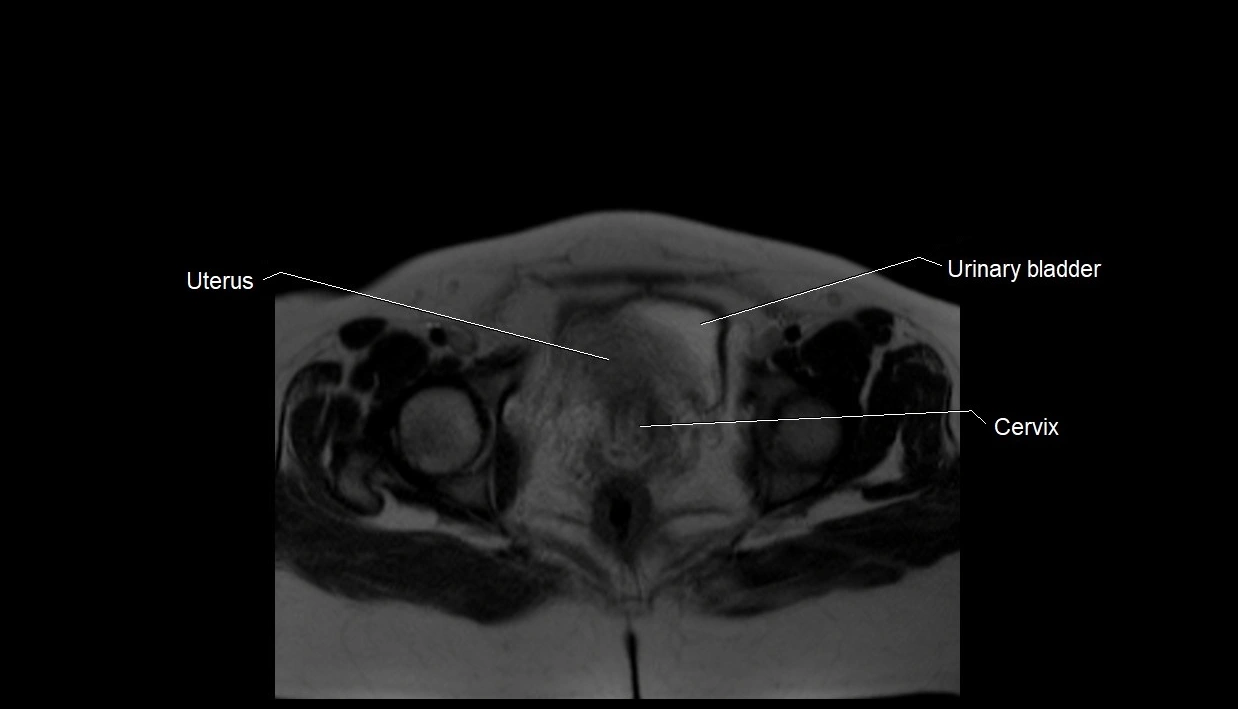

MRI Appearance

T2 HASTE (T2 GRE):

• Amniotic fluid shows very bright hyperintense signal

• Provides natural contrast against fetus and placenta

• Small particles (vernix) may appear as scattered hypointense foci within bright fluid

T1 GRE:

• Amniotic fluid shows low signal intensity (dark)

• Hemorrhage, infection, or proteinaceous content may cause focal or diffuse high signal intensity

MRI image

image